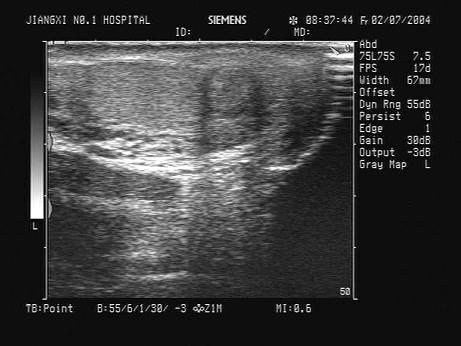

问题 某患者左侧阴囊下部疼痛不适3天,曾患前列腺炎,无外伤史,无结核病史,超声声像图如下,最可能的诊断为?(?)

选项 A.睾丸肿瘤 B.附睾尾炎性包块 C.睾丸炎 D.附睾结核 E.附睾肿瘤

答案 B